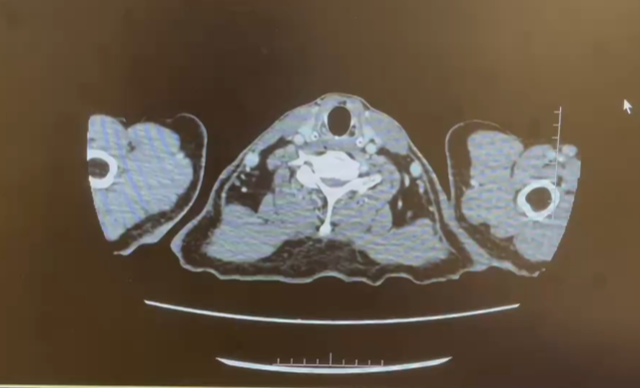

CT 肾脏平扫增强三维+肾血管成像 CTA+CTV,CT 肺部平扫+肺动脉成像 CTA

1.右肾上极稍低密度肿块灶及肾盂、输尿管上段壁明显增厚:考虑恶性病变,伴右肾静脉-下腔静脉-左肾静脉起始部癌栓形成可能性大,请结合临床。

2.右中肺外侧段肺动脉、左肺动脉干、左上下肺动脉多发栓塞。

3.左肺上叶尖后段混杂磨玻璃结节,LU-RADS 4B类,建议多学科会诊。

4.支气管炎。双肺下叶胸膜下少许炎症。

5.甲状腺双侧叶强化减低灶,建议结合超声检查。

6.左侧肾上腺结合部、内侧肢局限性增粗,意义待定。

日期:2024.5.29

双靶治疗(2个月)

双靶治疗(4个月)

2024.6.12 行根治性肾切除+腔静脉瘤栓取出术